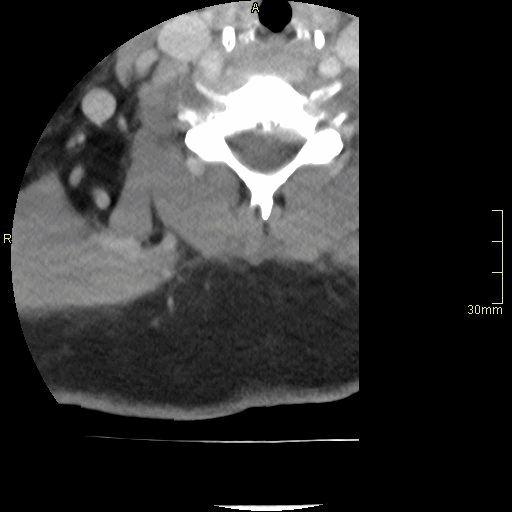

CT Thoracic Spine Contrast- Soft tissue window (axial)